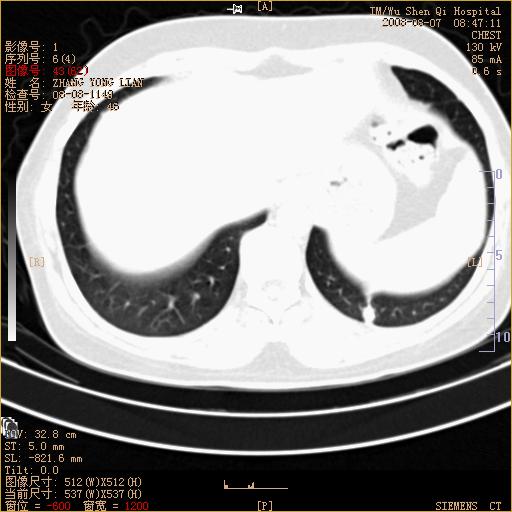

标题: CT15050:女,46岁,咳嗽胸痛一月余 [打印本页]

标题: CT15050:女,46岁,咳嗽胸痛一月余

纵隔窗没发全,左下肺近胸膜处结节。有长毛刺,纵隔淋巴结增大,不排除恶性病变。

考虑左肺下叶后基底段周围型肺癌伴纵隔淋巴结转移可能性大。

左下肺ca并纵隔及左肺门区淋巴结转移。

1)考虑左肺下叶后基底段周围型肺癌伴纵隔淋巴结转移。2)脾内低密度灶,性质待定;不排除转移瘤可能。